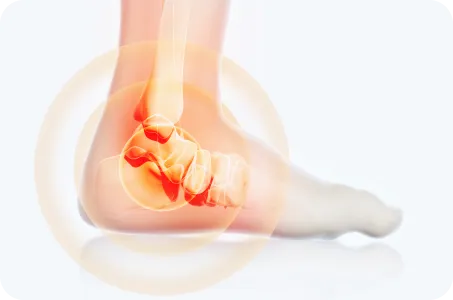

발목염좌

습관성 발목염좌는 일상생활이나 운동을 할 때 발목을 자주 접질리는 증상입니다.

발목관절을 지지하고 있는 인대에 비정상적인 외부 힘이 가해져 손상되거나 과하게 긴장되어 심한 경우에는 인대가 끊어진 상태를 말합니다.

원인

• 발목을 심하게 비틀리거나 접질렀을 때

발목 관절을 지지하는 인대들의 손상으로,

만성 발목염좌로 이환될 수 있습니다.